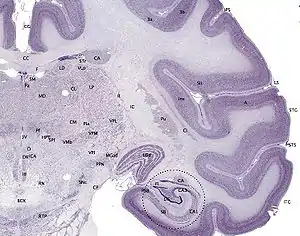

Cerebral cortex

The cerebral cortex is typically described as comprising three parts: the sensory, motor, and association areas. These sensory areas receive and process information from the senses. The senses of vision, audition, and touch are served by the primary visual cortex, the primary auditory cortex, and primary somatosensory cortex. The cerebellar cortex is the thin gray surface layer of the cerebellum, consisting of an outer molecular layer or stratum moleculare, a single layer of Purkinje cells (the ganglionic layer), and an inner granular layer or stratum granulosum. The cortex is the outer surface of the cerebrum and is composed of gray matter.[1]